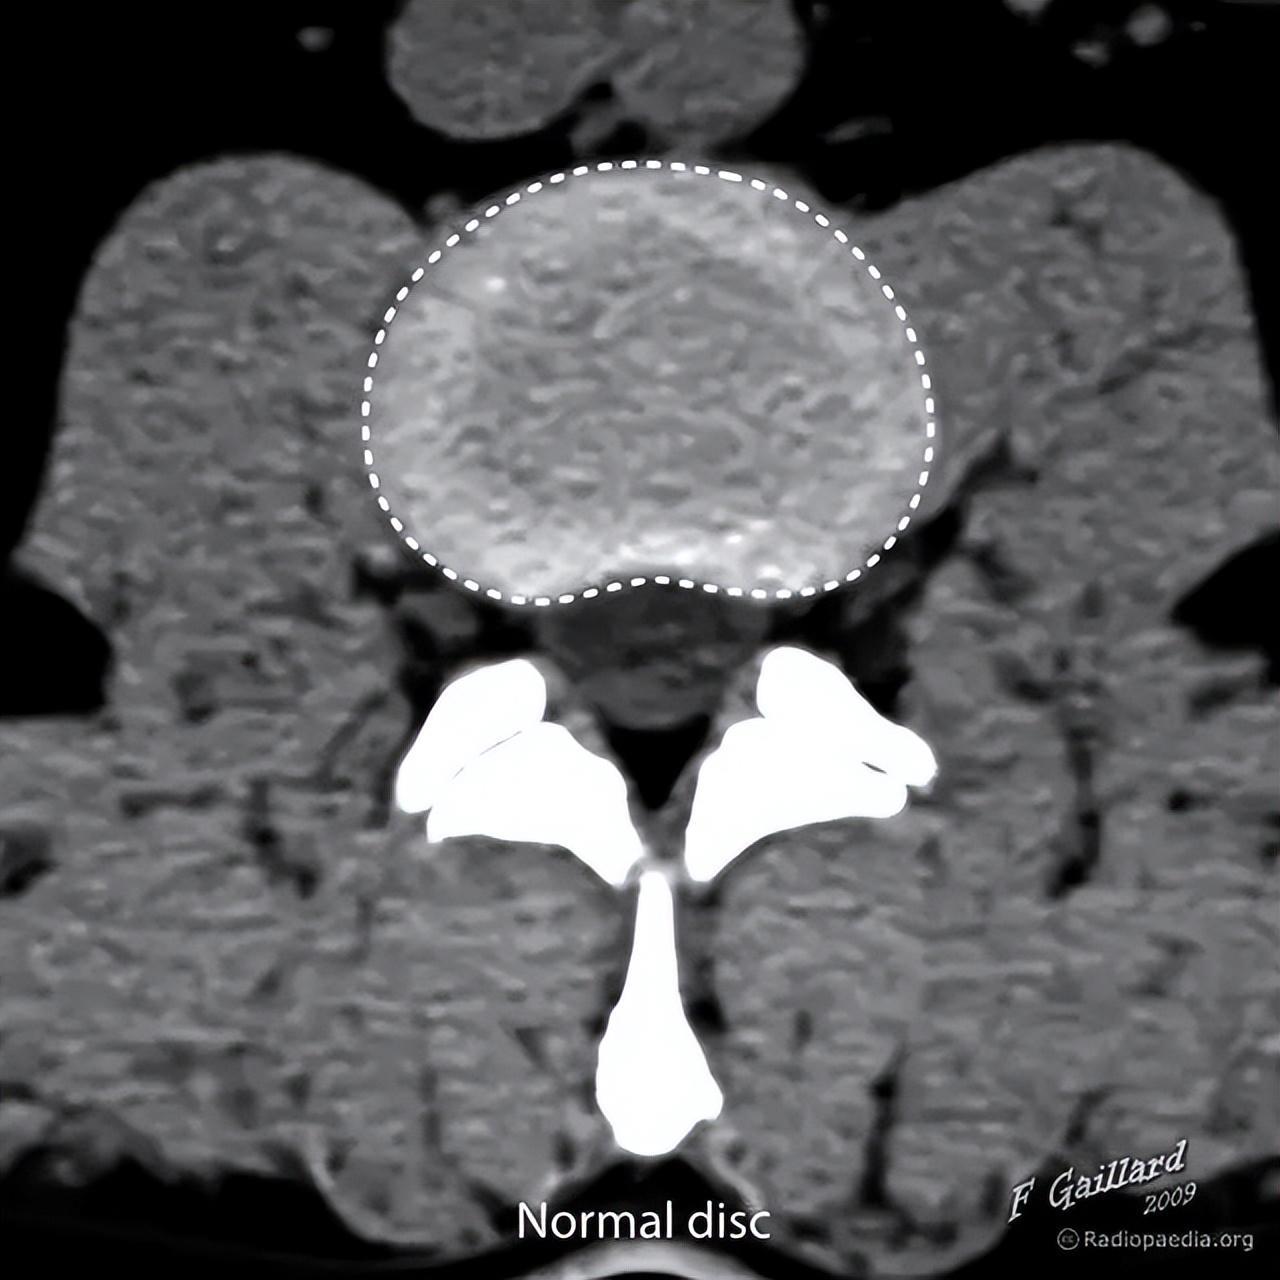

此为影像学图像,正常椎间盘(浅灰色区域)的周围不超出椎体边缘